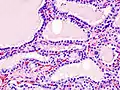

Hyperthyroidism is one of the most common endocrine conditions affecting older domesticated housecats. In the United States, up to 10% of cats over ten years old have hyperthyroidism.[60] The disease has become significantly more common since the first reports of feline hyperthyroidism in the 1970s. The most common cause of hyperthyroidism in cats is the presence of benign tumors called adenomas. 98% of cases are caused by the presence of an adenoma,[61] but the reason these cats develop such tumors continues to be studied.

The most common presenting symptoms are: rapid weight loss, tachycardia (rapid heart rate), vomiting, diarrhea, increased consumption of fluids (polydipsia), increased appetite (polyphagia), and increased urine production (polyuria). Other symptoms include hyperactivity, possible aggression, an unkempt appearance, and large, thick claws. Heart murmurs and a gallop rhythm can develop due to secondary hypertrophic cardiomyopathy. About 70% of affected cats also have enlarged thyroid glands (goiter). 10% of cats exhibit "apathetic hyperthyroidism", which is characterized by anorexia and lethargy.[62]